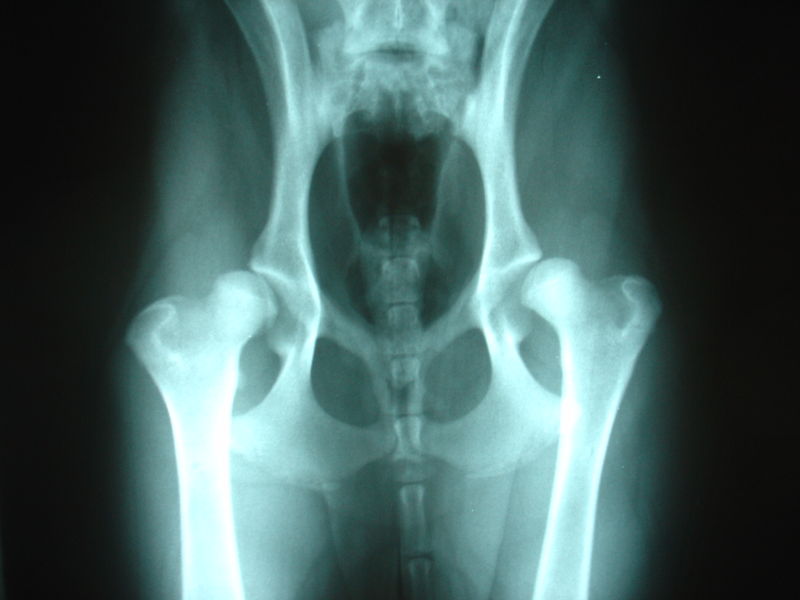

The only way to accurately diagnose HD is by radiography ( x-ray). Hip dysplasia is a developmental disease, meaning that it is not present at birth, but develops with age; it normally does not appear at all in x-rays of puppies or young cavaliers.

Cornell's specialists explain that, in a normal hip joint, the head of the femur fits snugly into the joint socket, or acetabulum, but in the dysplastic joint, the femoral head conforms poorly to the acetabulum. More space is evident between the bones. Displacement of the femoral head is the hallmark of the disease. Joints are evaluated using the DLS score. This measurement, expressed as a percent, is calculated from the radiograph and represents the percent of the femoral head covered by the acetabular rim. The greater the coverage, the higher the DLS score, and the healthier the hip joint. The DLS test may be carried out by the dog's regular veterinarian. See details here.